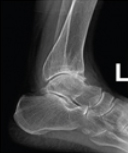

발목관절 전치환술

골관절염, 외상으로 인한 관절염 류마티스성 관절염 발생시 관절의 손상된 부분을 인체공학적으로 고안된 인공관절로 대체하여 원래의 신체구조를 복원시키고 통증을 완화해주는 수술입니다.

- 수술전